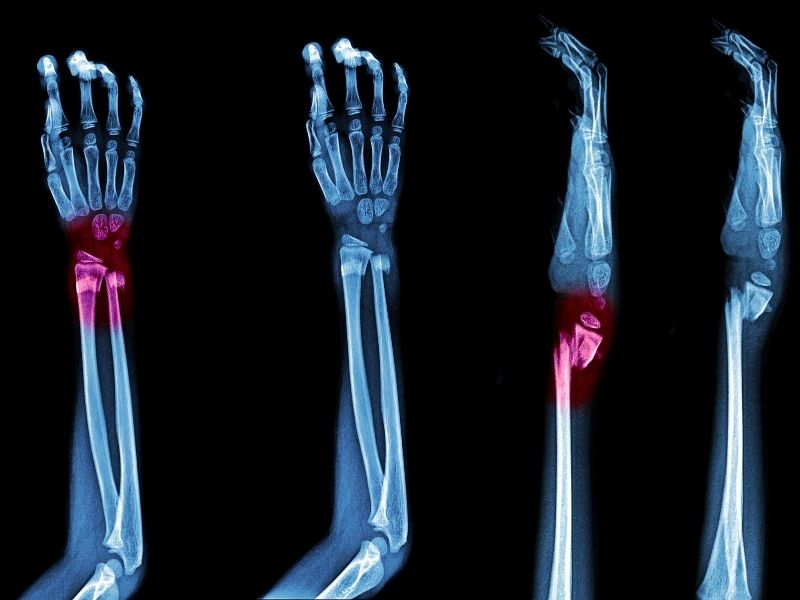

Kapalı intramedüller çivileme teknikleri: Bacak ve kollardaki uzun kemiklerin eklem içi dışındaki kırıklarının (basit-parçalı) büyük bölümünde uygulanan, kırık hattının açılmadan, 2-3 cm lik kesilerden yapılan ve kırık iyileşme süresini kısaltan tekniklerdir.

Uyluk kemiği kırıklarında kalçadan, kaval kemiği kırıklarında dizin hemen altından, üst kol kemiği kırıklarında omuzdan, önkol kemikleri kırıklarında dirsek ve el bilekten yapılan birkaç santimetrelik kesilerden kemik içine yerleştirilen çiviler kırığı çok etkin bir biçimde tesbit etmekte, yukarıdaki dezavantajların hiçbirini taşımamakta, alçı gibi ek dış tesbit gereksinimi genellikle olmamaktadır.